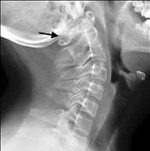

Клинические проявления, сопровождающие различные варианты ассимиляции атланта, и данные неврологического осмотра позволяют неврологу заподозрить нарушения, локализующиеся в шейном отделе позвоночника и краниовертебральной области. Для выявления ассимиляции атланта необходимо проведение рентгенографии позвоночника в шейном отделе с захватом затылочной кости. Такое исследование в прямой и боковой проекциях позволяет визуализировать место сращения. На стандартных и функциональных рентгенограммах часто обнаруживаются признаки нестабильности СIV-СV и СV-СVI, которой сопровождается ассимиляция атланта: изменение высоты межпозвонковых дисков, смещение позвонков и нарушение параллельности их суставных поверхностей.